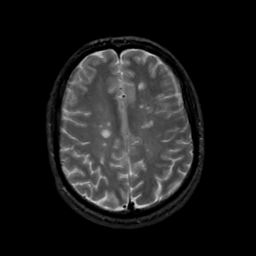

MR Study #19, August 25, 1991 -- Slice #35

[Home][Help][Clinical][Tour 1][Tour 2] Slice 35